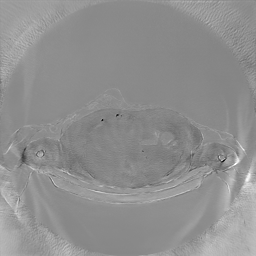

To assess the uncertainty of our method, we performed multiple reconstructions using different random seeds. As shown in Fig. 3, the ground truth and representative sampled images are presented in Fig. 3(a) and (b–d), respectively. The mean reconstruction and pixel-wise standard deviation across runs are displayed in Fig. 3(e) and (f). Only minimal differences are observed between reconstructions, indicating that I2SB produces highly consistent results. These findings confirm that, compared with classical diffusion models, I2SB substantially reduces uncertainty across repeated reconstructions.